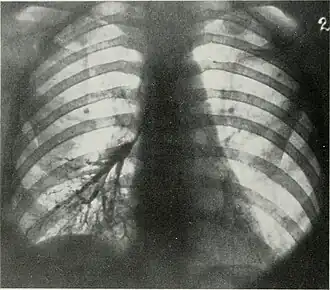

| Árvore bronquial inferior esquerda escurecida por depósitos de poeira metálica. | |

Siderose ou Pulmão do soldador é uma intoxicação caracterizada por depósitos de poeira de ferro nos tecidos humanos. Geralmente se refere a doença pulmonar causada pela inalação de óxido de ferro em trabalhadores de siderúrgicas, por isso o apelido "pulmão de soldador". Atinge principalmente trabalhadores de mineradoras de hematita, soldadores e trabalhadores que manipulem pigmentos com óxido de ferro. [1]